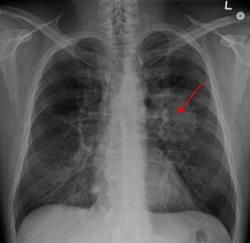

![]() Ko'krak qafasi rentgenogrammasi o'pkada o'sma aniqlangan | |

Oʻpka saratoniga shubha qilingan bemorlar oʻsmalarning mavjudligini, hajmini va joylashishini aniqlash uchun sinamalar va testlar oʻtkazish zarur. Birinchi navbatda oʻpka ichidagi oʻsma izlash uchun koʻkrak qafasi rentgenogrammasini oʻtkaziladi. Rentgenda oʻsmadan tashqari atelektaz, pnevmoniya aniqlanishi mumkin. Keyinchalik kompyuter tomografiyasi (KT) tekshiruvi oʻtkaziladi, bu tekshiruvda oʻsmalarning oʻlchamlari va joylashuvi aniqlanadi. Oʻpka saratoniga aniq tashxis qoʻyish uchun gumon qilingan toʻqimalarning biopsiyasi, saraton hujayralari uchun gistologik tekshiruv zarur. Oʻpka saratoni oʻsmalarining joylashishini hisobga olgan holda, biopsiyalarni koʻpincha minimal invaziv usullar bilan oʻtkazish mumkin: toʻqimalarni olish mumkin boʻlgan optik tolali bronxoskop (baʼzan endobronxial ultratovush yordamida), nozik igna aspiratsiyasi shular jumlasidan. Odatdagi biopsiya prosedurasini xohlamaganlar uchun suyuq biopsiya (yaʼni baʼzi tana suyuqligi namunasi) olinib tekshirilishi mumkin. KT saraton tarqalishi darajasini baholash uchun ham qoʻllanadi. Koʻpincha tanadagi metastazlarni aniqlash uchun pozitron emissiya tomografiyasi (PET) yoki kombinatsiyalangan PET-KT skaner tekshiruvi qoʻllanadi. PET skanerlash miyada nisbatan kam maʼlumot berganligi sababli, katta oʻsmalar boʻlgan bemorlarda miyani metastazlarni tekshirish uchun magnit-rezonans tomografiya (MRT) tavsiya qilinadi. Tomografiyada nomalum tarqalish aniqlansa uning saraton ekanligini tasdiqlash uchun biopsiya qilinadi. Oʻpka saratoni koʻpincha miya, suyaklar, jigar va buyrak usti bezlariga metastaz beradi. Oʻpka saratoni koʻpincha koʻkrak qafasi rentgenogrammasida oʻpka tuguni koʻrinishida tasvirlanadi. Biroq bu holat nafaqat saratonda boshqa koʻplab kasalliklar, shu jumladan metastatik saraton, gematomalar, gistoplazmoz yoki koksidioidomikozda ham uchraydi.